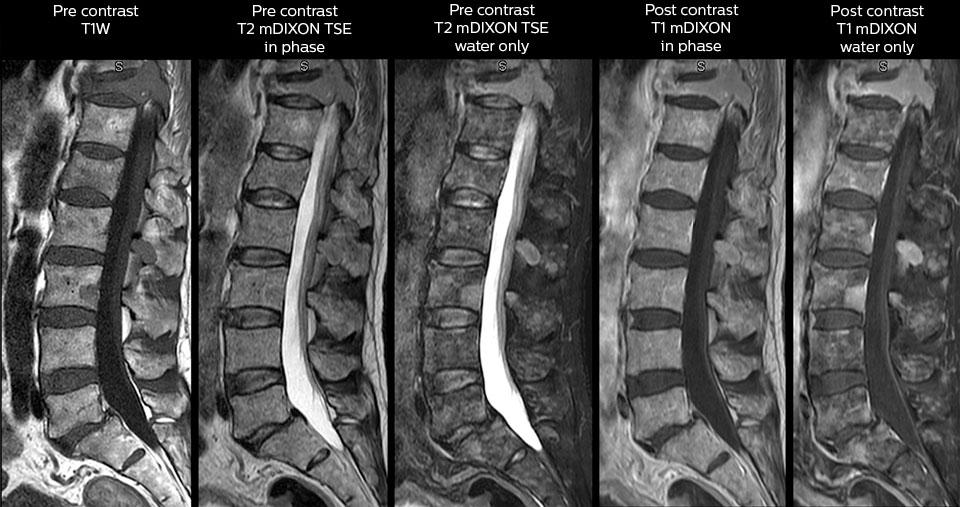

“We use mDIXON TSE extensively in our spine imaging in the emergency room,” says Dr. Karis. “It’s particularly nice in that it is very robust with regard to susceptibility type of problems that would come up with traditional spectral fat-saturated images; these problems are essentially eliminated with the mDIXON technique. In our ED environment it’s really nice to have the fat-free imaging that goes along with the mDIXON technique.

“For the thoracic and cervical spine routine non-contrast exam, for example, we perform one mDIXON T2 TSE sequence, which provides us with two outputs: the fat-and-water-together T2-weighted images, as well as the water-only sagittal T2-weighted images. And then we also perform an axial gradient echo exam.”

Cervical spine routine exam

This patient presented with headache that was worse with neck flexion and we see a Chiari 1 malformation with low-lying cerebellar tonsils as well as some degenerative cervical thrombolytic change.